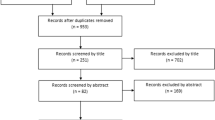

Of the identified 120 shoulders (120 patients), 7 patients (6%) were revised. Three (2%) of them because of superior glenoid dislocation (8, 15 and 36 months), two (2%) because of greater tuberosity displacement (1 and 2 months), one (1%) for a posttraumatic humeral fracture (24 months), one (1%) for an acromion fracture (3 months). Additionally, 14 patients (11.6%) were unable to travel for further examination because of high age or poor health status and 5 (4%) patients had passed away before regular follow-up, all unrelated to the surgical procedure. These twenty-six patients (study group) were included in the failure analysis but had to be excluded from further clinical and radiological analysis (Fig. 1).